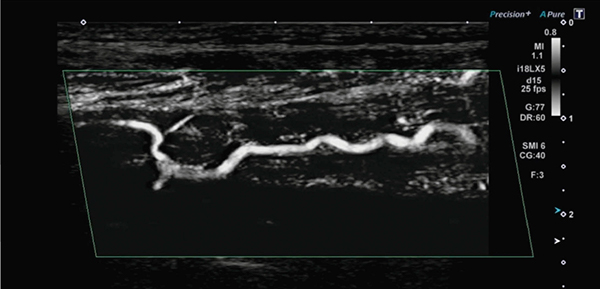

“Superb Micro-vascular Imaging”(以下,SMI)は,当社独自のアルゴリズムを用いて低流速の可視化を実現した手法である。SMIでは,組織の動きと重なっているような低流速の血流を,組織の動きの特徴を解析して分離することで,従来のカラードプラ法と比べ,モーションアーチファクトが大幅に減少した血流像が表示できる。SMIの表示法として,モノクロの表示の“monochrome SMI(mSMI)”とカラー表示の“color-coded SMI(cSMI)”とがある。また,SMIは,従来のドプラ法と比較して,高分解能,高フレームレートかつ低ノイズを実現し,それゆえこれまで検出困難であった低流速の血流を高精細に描出できる血流表示法でもある。実際の下肢動脈のSMI像においてもノイズを抑え,高分解能に血流が描出されていることがわかる(図3)。

図3 閉塞性動脈硬化症のSMI像